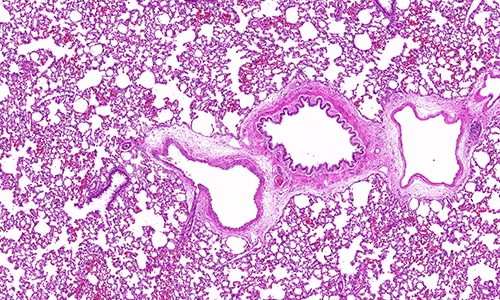

在病理学领域,HE染色(Hematoxylin and Eosin Staining)作为一种经典的染色方法,被广泛应用于组织样本的观察和分析。HE染色不仅为病

2023/12/15详情 >